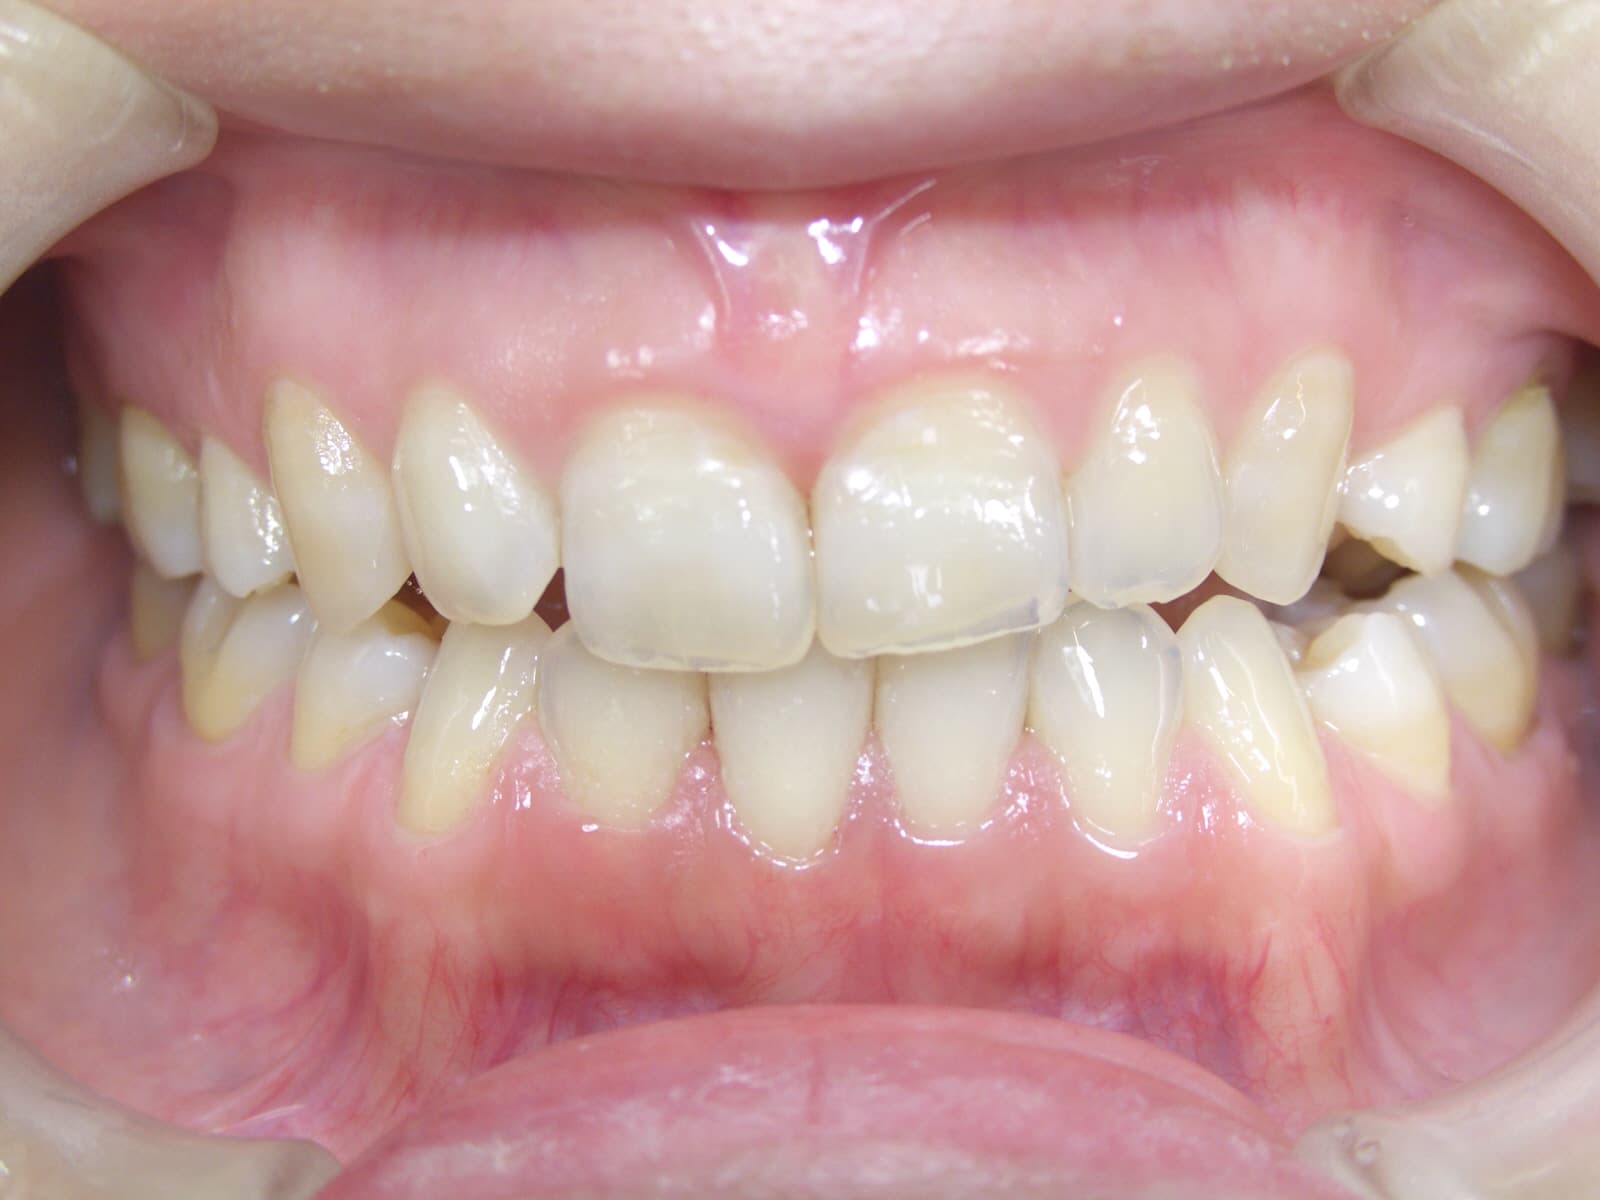

治療した歯を長く持たせたい 歯周病治療

こんにちは。 衛生士の山崎です。 歯周専門治療の症例をご紹介します。 30代女性の方です。 オールセラミックの被せ物をした後、 長く良い状態でお使いいただくために、 歯周病専門治療を行いました。 &n…